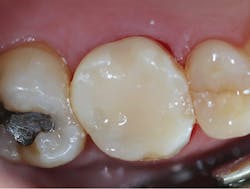

A 56-year-old male presented with pain on chewing. It was determined that several fractures had developed in the upper-left first molar, which was confirmed by bite-stick test (figure 8). A radiographic exam was within normal limits.

Figure 8: Patient presentation

Upon achieving local anesthesia, an impression was made for provisional crown fabrication using a triple tray and monophase VPS impression material (V-Posil Mono Fast , Voco; figure 9). The tooth was then prepared for a crown using a flowable, dual-curing, nano-hybrid core build-up material (Grandio Core Dual Cure, Voco; figure 10).

Figure 9: Impression for provisional crown fabrication

Figure 10: Tooth preparation